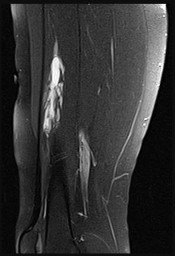

This patient has a dedifferentiated liposarcoma within a preexisting atypical lipomatous tumor. The imaging demonstrates a large fatty mass with increased internal septations proximally (the atypical lipomatous tumor) and a solid enhancing mass distally (the dedifferentiated portion). A biopsy reveals a high-grade liposarcoma. The other diagnostic responses do not reflect sarcomatous transformation of the lesion.

Surgical treatment of a high-grade sarcoma involves wide surgical resection. Radiation decreases local recurrence but does not clearly influence overall survival. The role of chemotherapy in high-grade soft-tissue sarcomas remains investigational; there is a modest (8%-15%) associated improvement in overall survival.

Intramuscular lipomas and atypical lipomatous tumors are treated with marginal resection alone. Radiation therapy for soft-tissue sarcomas may be given before or after surgery. When administered before surgery, patients have a higher wound complication rate but better long-term function attributable to lower rates of lymphedema, fibrosis, and contractures.